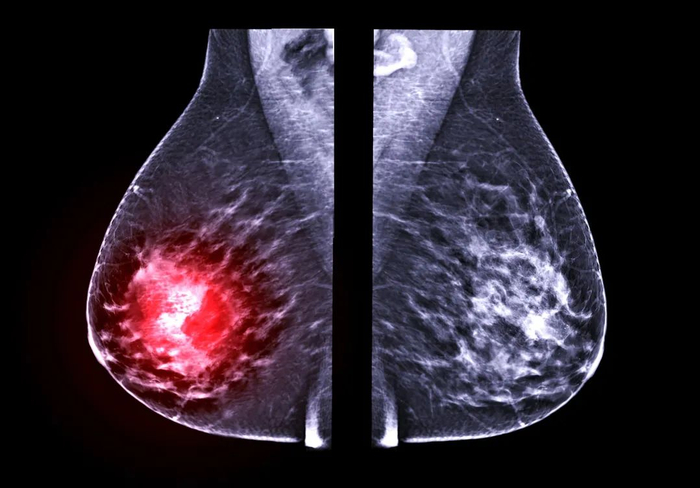

首先要明确一点,在我们体检报告单上的“乳腺结节”并不是疾病名称,而是一种影像描述。

B超、X线、CT等影像检查发现的乳腺小肿块,在性质不明确时,都可以被叫做乳腺结节[1]。

这种小肿块可能是增生所形成的组织改变,也可能是乳腺良性肿瘤,甚至可能是乳腺癌。

如何评判乳腺结节的恶变概率呢?其实我们可以通过一项报告来观察乳腺结节恶变的风险等级:BI-RADS。

BI-RADS是评价乳腺结节良性、恶性的统一分级标准,用0~6进行表示,级数越高,恶性程度越高。

当诊断结果在BI-RADS-4类以上,考虑有较高的恶变几率,应尽快前往乳腺外科就诊,请医生进行详细评估。